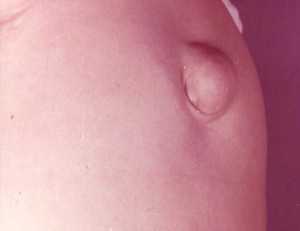

Пупочная грыжа – патологическое состояние, при котором части внутренних органов выпирают за брюшную стенку через отверстие в пупочном кольце. Под воздействием разных факторов происходит расширение пупочного кольца. Мышечные ткани вокруг него становятся атрофированными. Оно становится неустойчивым к воздействию внутрибрюшного давления.

На начальном этапе пупочная грыжа незначительная. Когда больной принимает лежачее положение, она может с легкостью вправиться обратно. Постепенно кольцо пупка расширяется, грыжа увеличивается.

Что представляет собой грыжа пупочная у женщин: фото и описание

У некоторых женщин по тем или иным причинам часть внутренних органов выходит за пределы брюшной стенки через пупочное кольцо. Как правило, это участки толстого или тонкого кишечника, реже сальника или других органов. Именно так формируется грыжа пупочная у женщин. Фото демонстрирует, как выглядит грыжевой мешок.

Естественно, заметить появление болезни на ранних этапах не так уж легко, но по мере развития грыжу можно увидеть даже невооруженным взглядом. В современной хирургии это одна из самых распространенных проблем, от которой нередко страдают даже новорожденные девочки. Если же речь идет о взрослых женщинах, то грыжа, как правило, формируется после 40 лет, что связано с постепенным истощением соединительной ткани и ослаблением пупочного кольца.